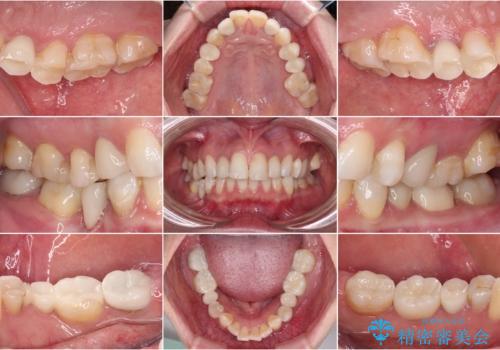

- クラウンから金属の土台が見えてきてしまったとのことで、作り替えを希望して来院された患者様です。

前歯や金属が露出している歯、痛みを感じる歯を中心に、オールセラミッククラウンにて補綴治療することとしました。

以前はセラミッククラウンのフレームとして金属が使用されており、歯肉の経年変化やセラミックのすり減りなどにより、金属が見えるようになってくることがあります。

現在は金属の代わりに強化セラミックを使用したオールセラミッククラウンが主流です。金属色が気になる方はご相談ください。